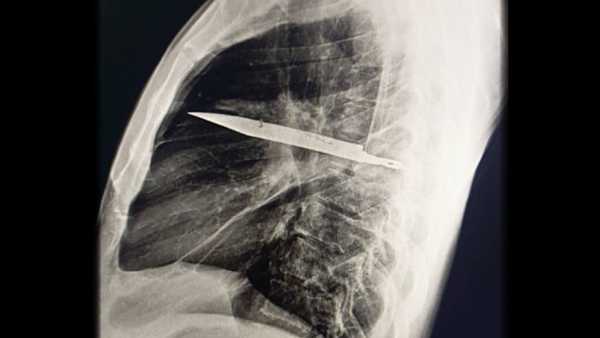

• A knife was embedded in a man’s torso, unbeknownst to him for 8 years

A knife was embedded in a man’s torso, unbeknownst to him for 8 years